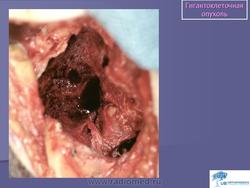

Гигантоклеточная опухоль.

1.gigantoslayd15.jpg1.gko_.slayd156.jpg2.gko_.slayd157.jpg3.gko_.slayd158.jpg4.gko_.slayd159.jpg